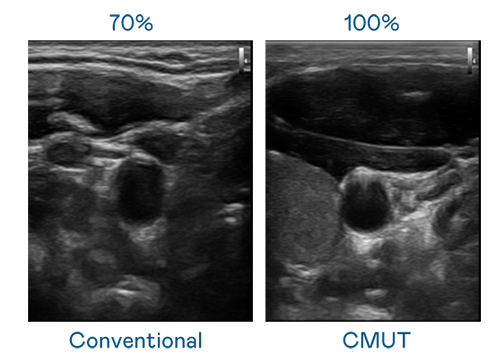

CMUT 技术是一种用电容式微机电元件来产生超音波讯号的技术。与传统 PZT 压电式技术相比,CMUT 频宽增加 30%,更宽频的超音波讯号让影像解析度大幅提升,是实现高影像品质医疗超音波扫描、促进精准医疗发展的关键技术。

大频宽带来超清晰影像

超音波影像的解析度高低,首先取决于探头能发出的讯号频宽。bfball百富策略 CMUT 可提供高清晰的超音波讯号,提供高频宽、高灵敏度、影像纹理细节更高的超音波影像,协助医护人员缩短影像判读时间及利用精准的医疗影像进行诊断。